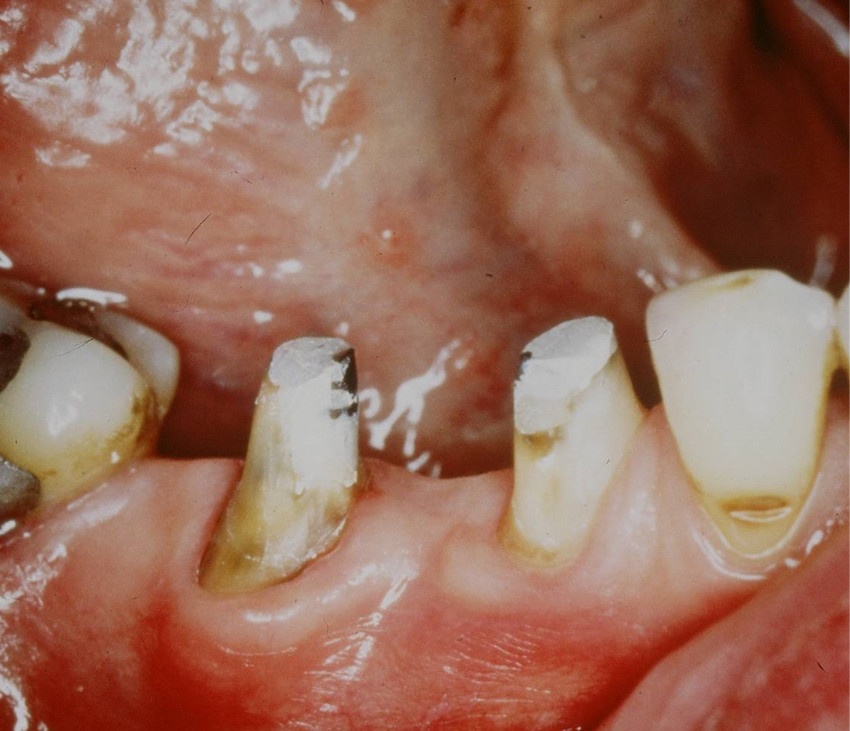

Eine absolute Extraktionsindikation stellt die Wurzellängsfraktur bei einwurzeligen Zähnen dar. Differenzierter zu betrachten ist die Wurzellängsfraktur eines mehrwurzeligen Zahnes. Bei entsprechend günstigen Voraussetzungen kann mitunter auch die Option einer Hemisektion in Betracht gezogen werden. In die Entscheidungsfindung sollten auch immer Überlegungen zur langfristigen Planung einfließen. Die prothetische Wertigkeit eines Molaren ist beispielsweise durch die Entfernung einer Wurzel deutlich herabgesetzt. Klinisch imponiert bei Längsfrakturen der sogenannte „Kamineffekt“. Bei zirkulär sonst unauffälligen Sondierungstiefen fällt man entlang des Frakturverlaufs mit der Messsonde in den osteolytisch entstandenen „Kamin“ (Abb. 13). Auch im hier dargestellten Fall (Abb. 16) war nach Auswertung aller relevanten Aspekte (Ursache, Prognose, langfristige prothetische Planung) die frühzeitige Extraktion Mittel der Wahl um die Voraussetzungen für eine anschließende Implantation nicht negativ zu beeinflussen.